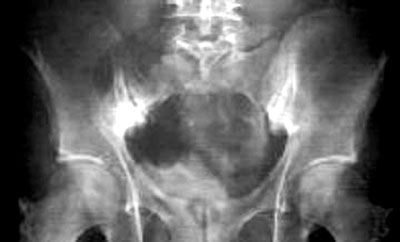

■在X光片之下,兩邊的胝骨關節同樣出現纖維化。